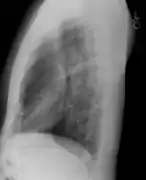

Placa lateral de tórax en el sujeto normal. El lado izquierdo del tórax se apoya sobre el cassette de la película radiográfica para impedir la magnificación del corazón. Las placas posteroanterior y lateral constituyen el "par radiográfico de tórax".